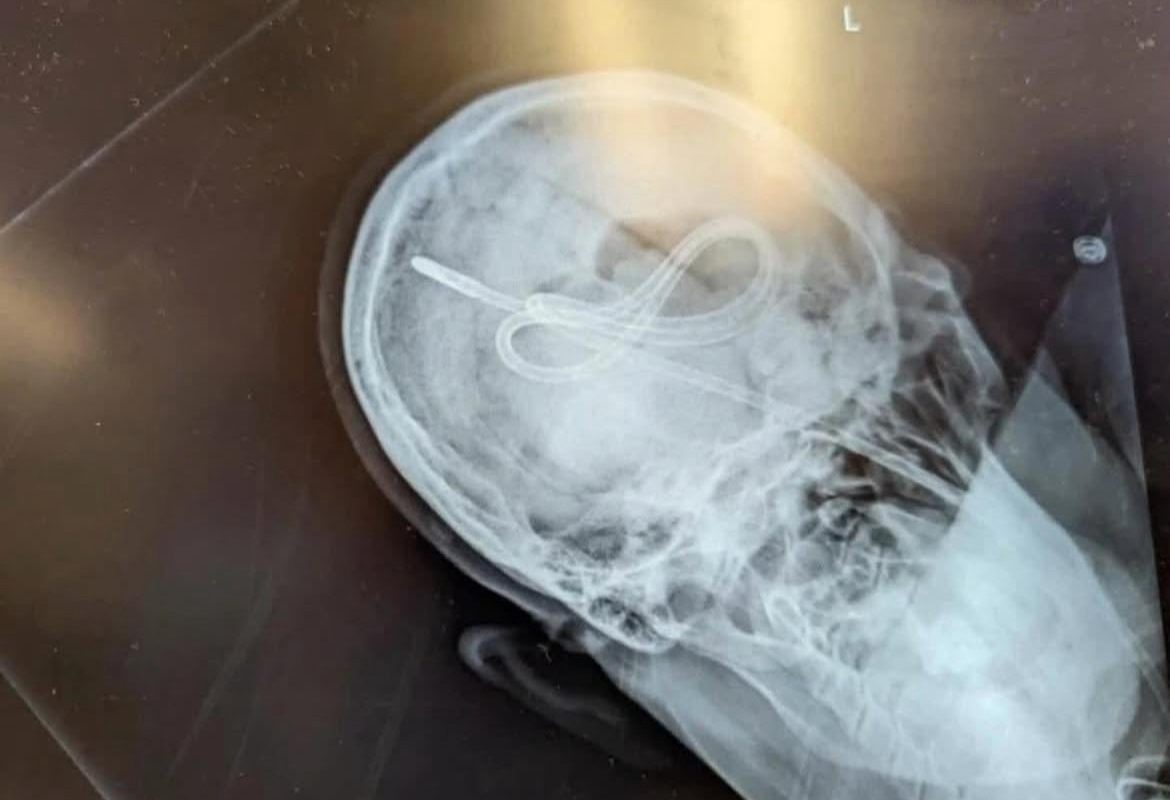

In the early 2000s, a patient with a traumatic brain injury required NG tube insertion for feeding. Due to skull fractures and compromised anatomy, the tube migrated upward instead of downward, puncturing the skull’s base and entering the brain cavity. Tragically, the mistake was confirmed only after the patient developed severe neurological symptoms, leading to irreversible damage or death (reports vary).

- A chest/abdominal X-ray showing the tube’s path below the diaphragm is the only foolproof way to rule out skull or lung penetration.